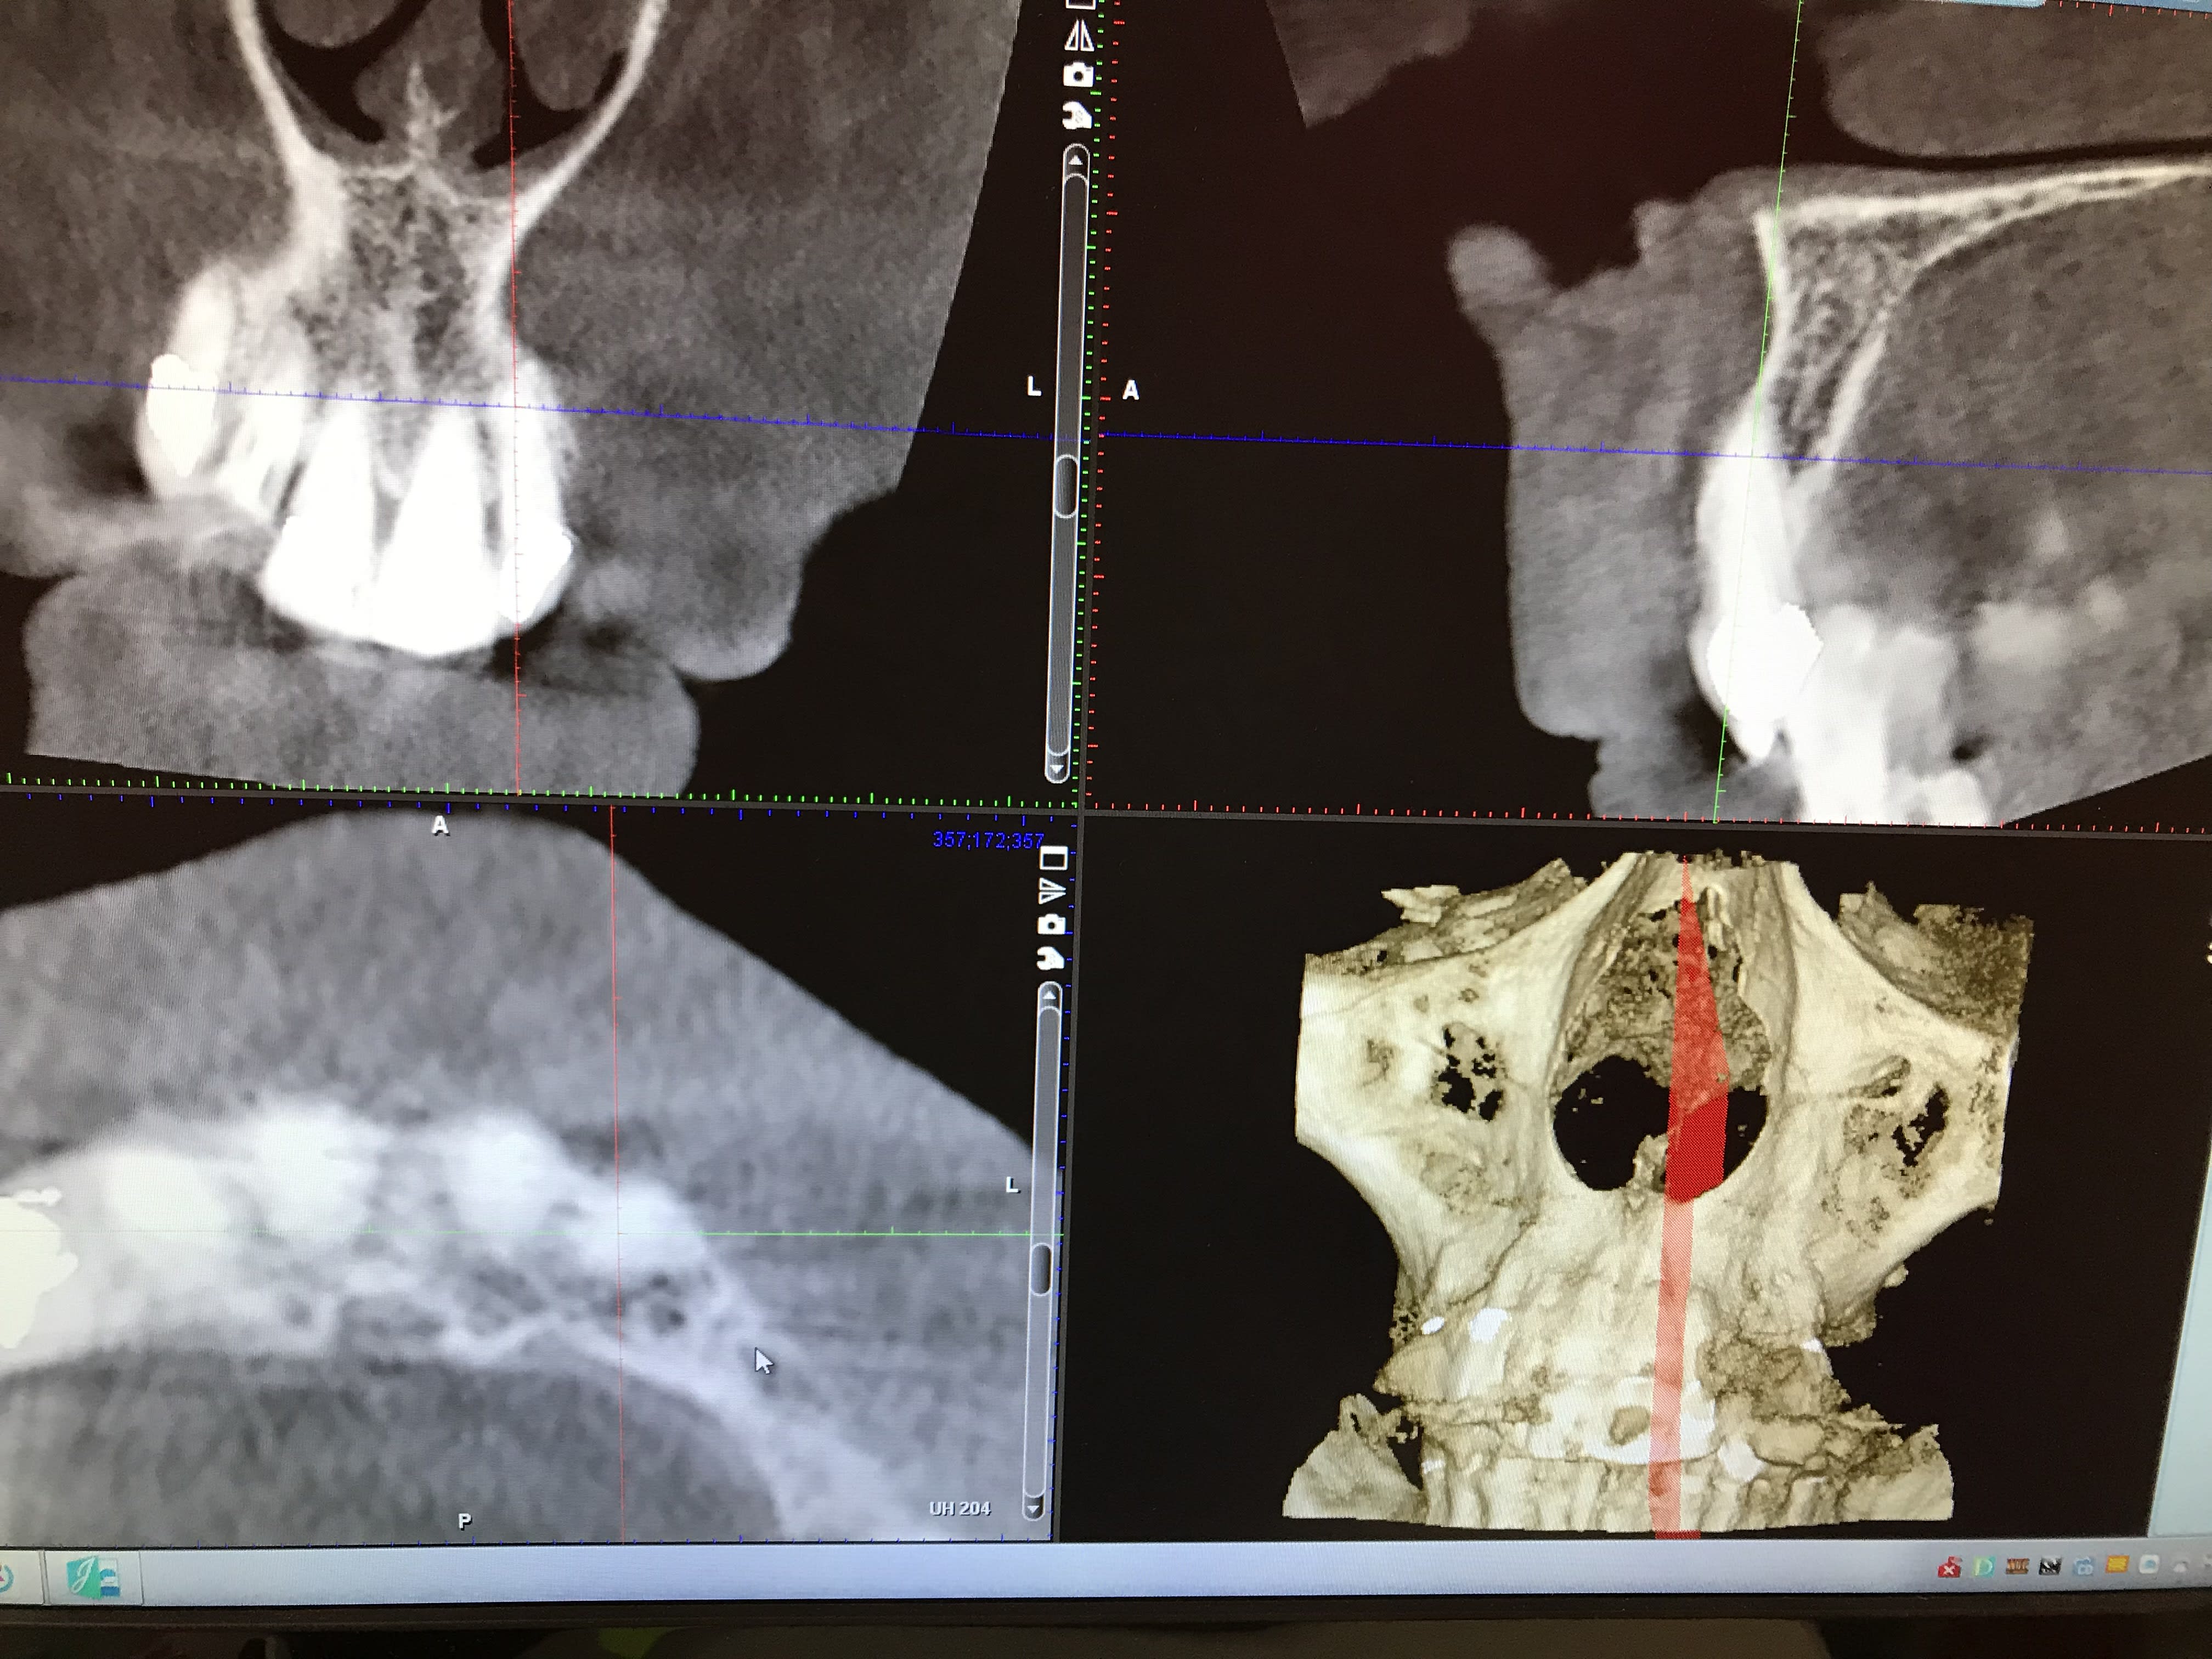

Patiente avec pilier de bridge 13 fracturé + 15 paro mobile + 25 paro mobile + 22 légèrement mobile. Les seules dents "viables" sur l'arcade sont 11, 21 et 22 et la 12 a été extraite entre temps.

Sur les coupes conebeam, très peu d'os au niveau de 13 et surtout 14 en épaisseur, un peu plus au niveau de 23 et 24 et pas assez d'os au niveau de 15 et 25 (présence des sinus).